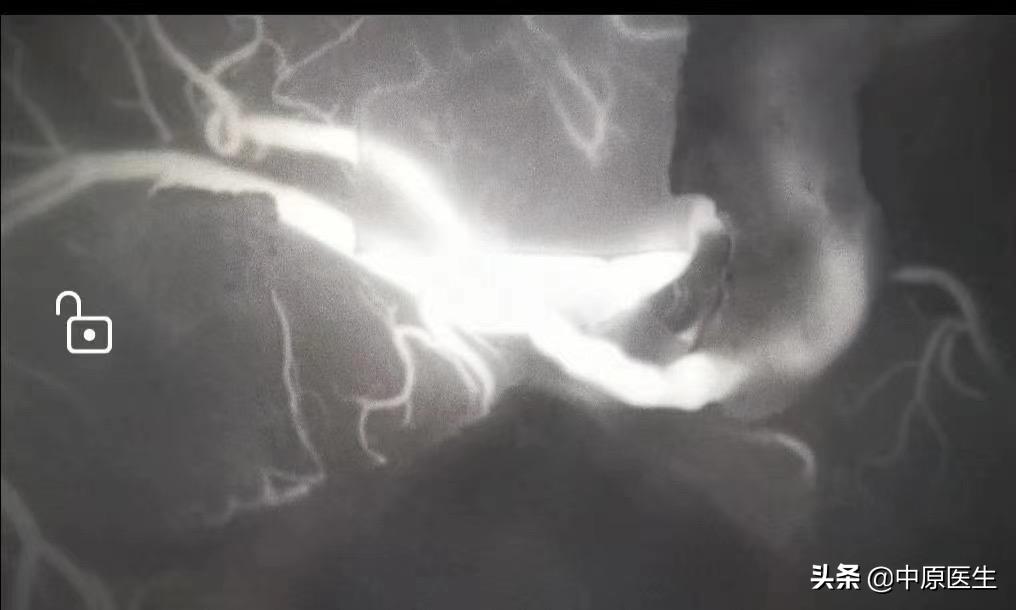

烟雾病又称自发性脑底动脉环闭塞症,是一组以双侧颈内动脉末端和(或)大脑前动脉、大脑中动脉起始部缓慢进展性狭窄以致闭塞,脑底出现代偿性异常血管网为特点的脑血管病。因其异常血管网在脑血管造影时形似"烟雾",故称“烟雾病”。

今天这个病人并无特殊性,严格讲,受体血管顶多为0.7毫米,并不理想,但还是“百折不挠”的缝合了11针,术中ICG通常良好。